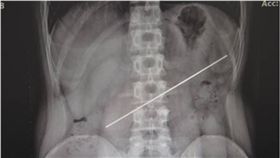

他打賭吞鋼條贏2萬 一年後倒賠7萬

得不償失!大陸一名1年前與朋友打賭,吞下20公分的鋼...

2018/04/26 15:41